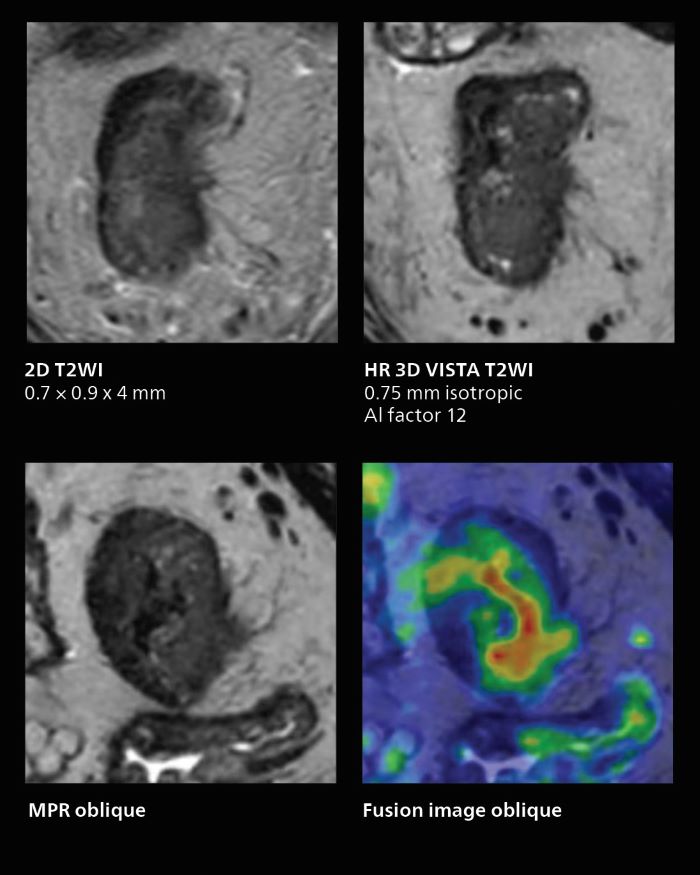

MRI of rectal cancer

In this patient MRI was done to help in diagnosing the depth of invasion. Performed on Elition X.

Notable improvement in diffusion-weighted imaging

With SmartSpeed, Kumamoto Chuo Hospital also has the ability to use EPI diffusion-weighted imaging (EPICS-DWI) with Compressed SENSE, which is an important step forward according to Dr. Katahira. “Before, our EPI diffusion was performed using SENSE, but now with Compressed SENSE it is possible to obtain very clear images,” he says. He also describes the benefit of being able to perform 3D diffusion-weighted imaging. “Previously, we only had DWI images in one direction to make a diagnosis. Now, we can do something that was not possible before: performing a DWI volume acquisition so that multiplanar reconstruction can be used, allowing us to look at scan results from all directions to make the diagnosis,” Dr. Katahira says. “What used to be a diagnosis based on just cross-sectional images, can now be based on a volume image. This is a dramatic improvement for us, because it is now possible to look at slices in various cross section directions. For example, the presence or absence of venous invasion is very important in rectal cancer patients, because venous invasion can cause metastasis in the future. The ability to reconstruct images according to the direction of the blood vessels, allows us to see venous infiltration more realistically, which is a world of difference from what we were used to.”